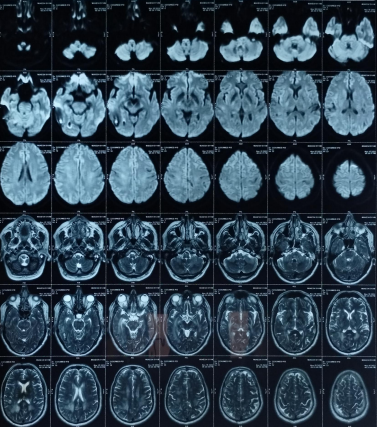

The patient’s routine blood investigations were normal. Serology for HIV, hepatitis B, C, and syphilis was negative. His MRI brain showed a parenchymal bleed in right temporo occipital regions with intra-ventricular leakage of blood and tiny petechial haemorrhage in brain parenchyma bilateral. extensive signal changes in cerebellar hemisphere, bilateral gangliothalamocapsular region, pons, midbrain and deep white matter of both cerebral hemisphere? Microangiopathy? CADASIL.

Early-onset dementia (onset before age 65) is a thought-provoking ailment with many possible causes, including early-onset familial Alzheimer’s disease, frontotemporal lobar degeneration, Parkinson’s dementia, Lewy body dementia, disorders of amino acid and organic acid metabolism, leukodystrophies, lysosomal storage diseases, disorders of metal metabolism, and mitochondrial diseases [6]. In our patient, the history, physical examination, laboratory investigations, and neuroimaging were not suggestive of these causes and prompted the search for a rare etiology. The most common MRI finding associated with CADASIL is basal ganglia and white matter hyperintensities in T2-weighted sequences that start as punctate or nodular foci and then often become confluent, extensive, and usually symmetrical, mainly in the periventricular region, anterior temporal pole, external capsule, the centrum semiovale, and frontal and parietal areas. In our patient, diagnosis was made mainly from MRI findings as seen in fig. 1, 2.

Fig. 2: Extensive hyperintensity on T2W/FLAIR sequence is seen in bilateral thalamus and basal ganglia, both cerebellar hemisphere, mid brain, pons and in deep white matter of both cerebral hemispheres